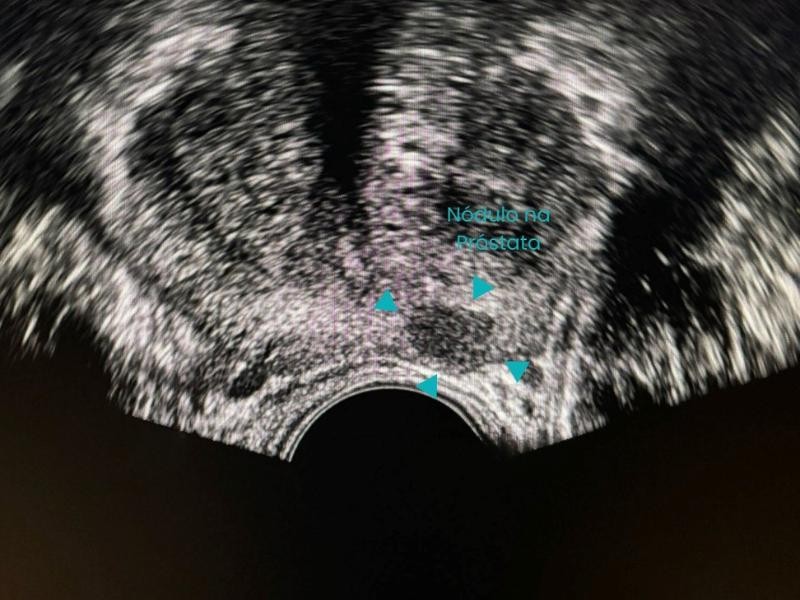

Conquistou o primeiro lugar no exame nacional da SOBRICE e se destaca em procedimentos minimamente invasivos, como ablação de tumores e biópsias guiadas. Atende nos melhores hospitais de São Paulo, incluindo o Hospital Nove de Julho e Vila Nova Star.